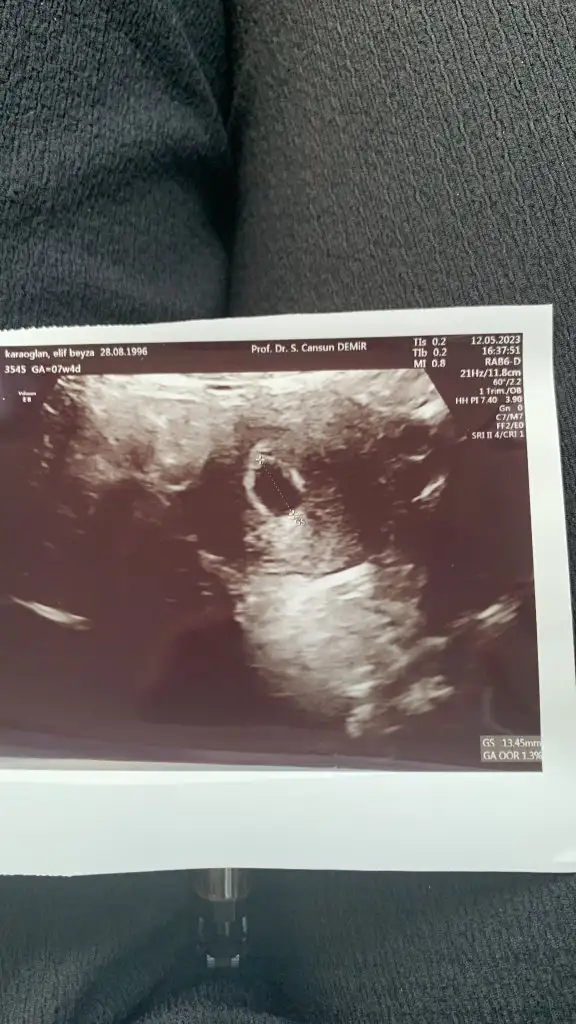

Şimdi buraya en son gittiğim doktorun ultrason görüntüsünü atacağım. Yolk sac varmı yok mu bunj anlayabilir miyiz. Belki bebeğim geriden geliyordur belki geç tutunmuştur bana, böyle umut etmek istiyorum.